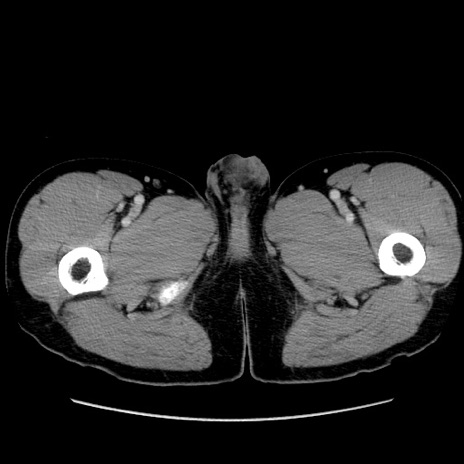

症例36(横断像)

【症例】20歳代 男性

【主訴】心窩部痛

【現病歴】今朝より上腹部痛あり。一旦軽快していたが再度出現したため救急要請。昨日夕に白身の魚を含む刺身を食べた。

【身体所見】BP 136/89mmHg、HR 74/min、BT 37.0℃、腹部:膨満、軟、心窩部に圧痛あり。反跳痛なし、筋性防御なし、腸雑音やや亢進あり。

【データ】WBC 17700、CRP 0.48